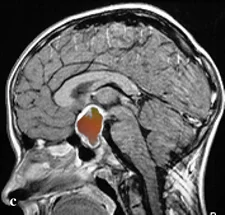

- Κρανιοφαρυγγίωμα: καλοήθης (WHO grade I) αλλά τεχνικά απαιτητικός όγκος της υπόφυσης/υποθαλάμου, με επίδραση στην όραση και στο ενδοκρινολογικό σύστημα.

Κρανιοφαρυγγίωμα: κατατάσσεται ως WHO grade I, αλλά η συμπεριφορά του επηρεάζεται από τη θέση και την πρόσφυση στον υποθάλαμο και την οπτική οδό. Υπάρχουν δύο ιστολογικοί τύποι: αδαμαντινοματώδη (συχνός στα παιδιά, με ασβεστώσεις και «motor oil» κύστεις) και θηλώδη (κυρίως σε ενήλικες).